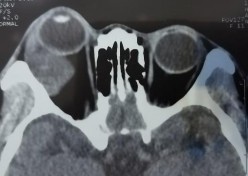

Bệnh nhân nam, 45 tuổi, 2M: sưng nề mi góc ngoài + sờ thấy khối u

Bệnh nhân sờ thấy khối u và sưng nề mi cách vào viện 8 tháng, không đau nhức (A, B). Tiền sử u lympho di căn phổi 1 năm đang điều trị. Hình ảnh cắt lớp vi tính toàn bộ hai tuyến lệ là khối tăng tỉ trọng, bờ đều, kích thước u MP 13 x 30 mm, MT 24 x 30mm, khối u đúc khuôn quanh nhãn cầu (C, D). Kết quả giải phẫu bệnh là u lympho ác tính (u lympho ác tính) (E: HE x 200, F: HE x 400). Bệnh nhân được điều trị bằng hóa trị.